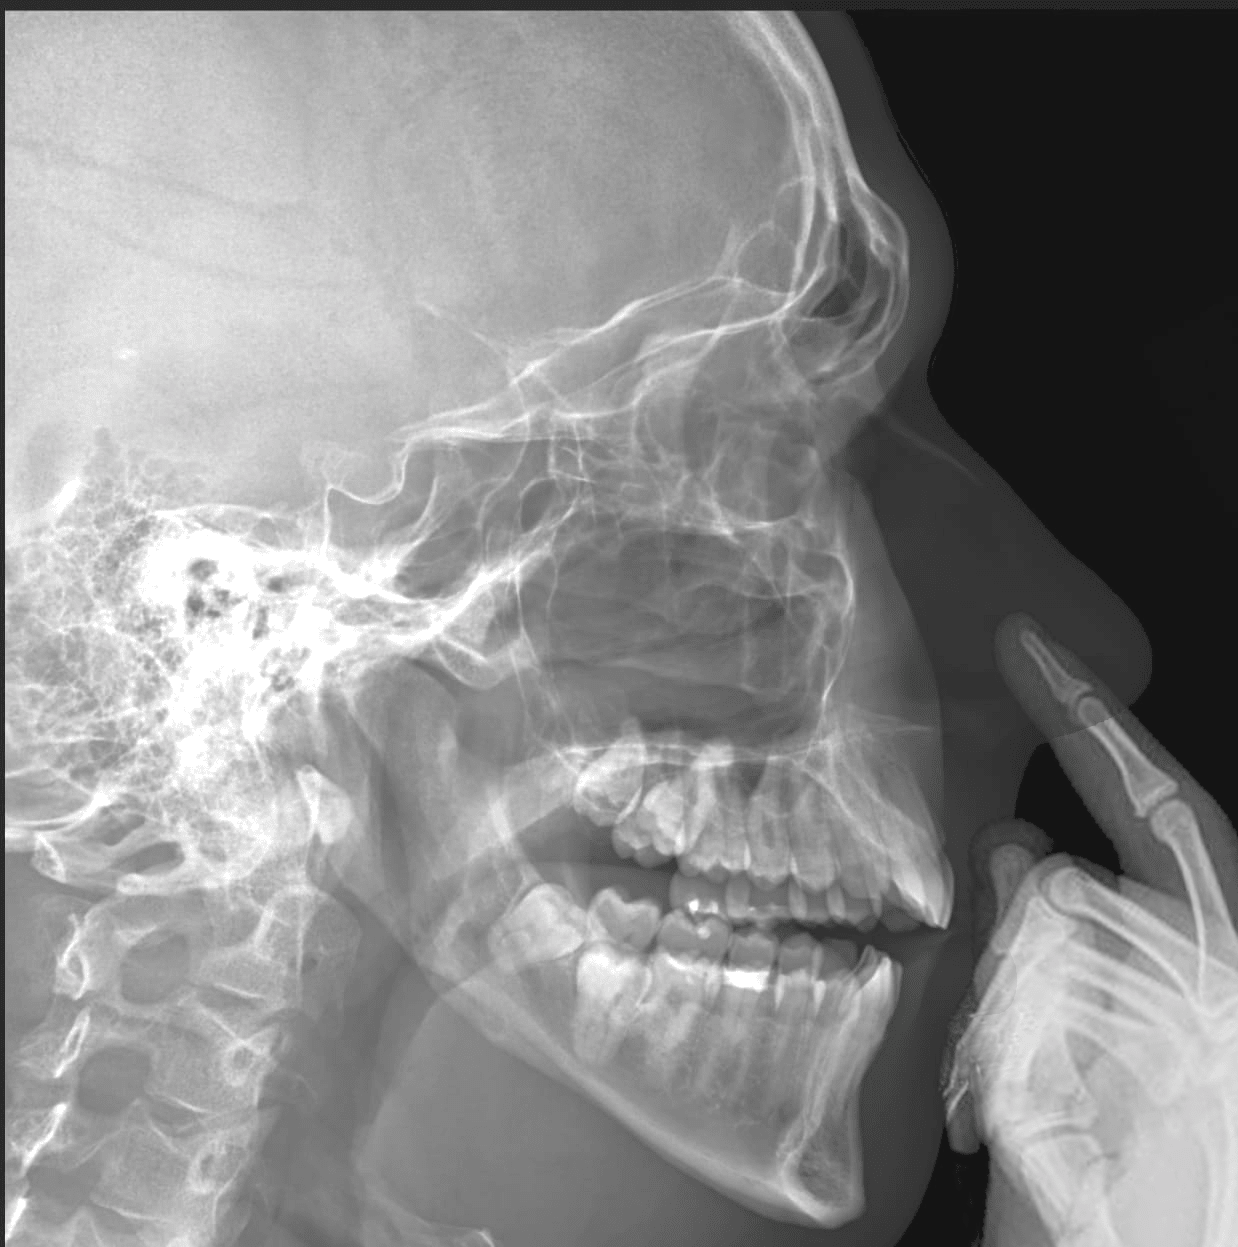

Just got my head xrayed for unrelated reasons. Check out my enlightened wisdom pointing in all which-ways

@Moose it’s weird to see your skull. Is it weird for you?

@katylava @Moose nnoooo it is totally cool to see ones skull and how it lines up with the outline of their face.

@Moose

@medz @Moose

@medz stop messing with my head!